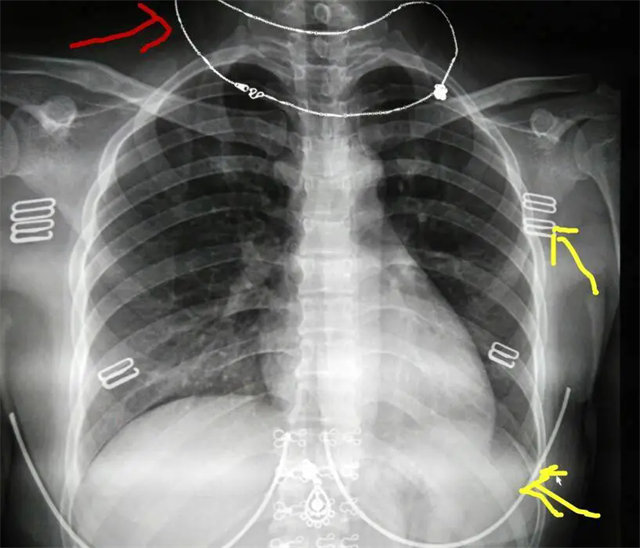

缺陷:兩肩胛骨未拉開肺野之外,吸氣不完全,且存在金屬飾品遮擋。

解決:去除金屬飾品及內(nèi)衣后重新按標(biāo)準(zhǔn)體位攝片即可。

缺陷:肩胛骨未完全拉離肺野,吸氣不完全,存在金屬偽影遮擋,略有聳肩,且肺尖顯示不好,圖像顆粒感較強(qiáng),管電流量不夠,信噪比偏低。

解決:去除金屬物品后,按標(biāo)準(zhǔn)體位,使患者雙肩旋前與前胸一并緊貼成像件,適當(dāng)調(diào)高mAs,然后深吸氣后屏氣曝光。